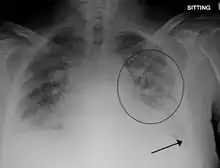

A chest x-ray showing pulmonary edema with bilateral pleural effusions.